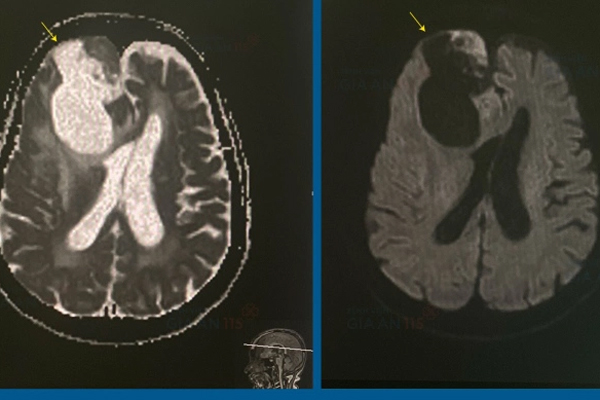

Khối u lớn người bệnh trên ảnh chụp MRI. (Ảnh: BVCC)

ThS.BS Phùng Đăng Khoa, khoa Ngoại, Bệnh viện Gia An 115 TP.HCM, cho biết, cụ H. nhập viện cấp cứu trong tình trạng lơ mơ, thực hiện y lệnh chậm. Kết quả MRI cho thấy người bệnh có khối u màng não kích thước lớn (63x45x52mm) chèn ép sừng trán não thất bên phải. Khối u chèn ép thần kinh là nguyên nhân gây ra các triệu chứng động kinh cục bộ như co giật hai tay, trợn mắt ở người bệnh. Tình trạng nguy cấp này đòi hỏi phải phẫu thuật ngay.